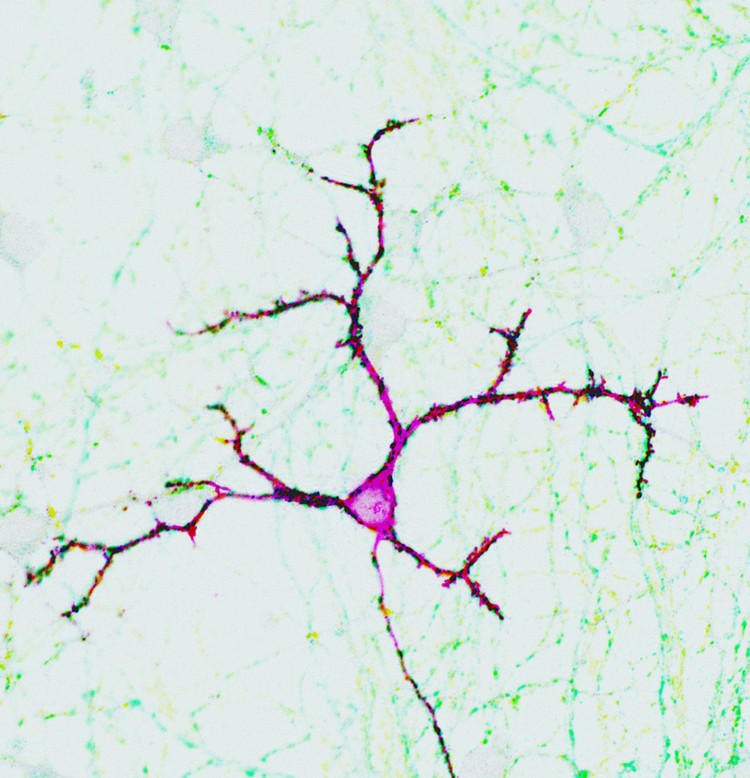

Neuron with synaptic contacts.

Neuron with synaptic contacts Biozentrum of UNIBAS

Scientists in Basel and Geneva have discovered that the difficulty in managing social interactions found in people with autism is due to poor maturation of the synapses, the part of neurons that allows them to communicate with each other.